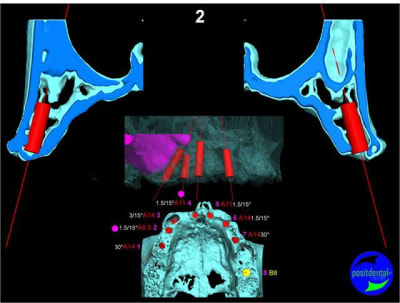

en attendant la pano voici les coupes de la S.I.A.O.